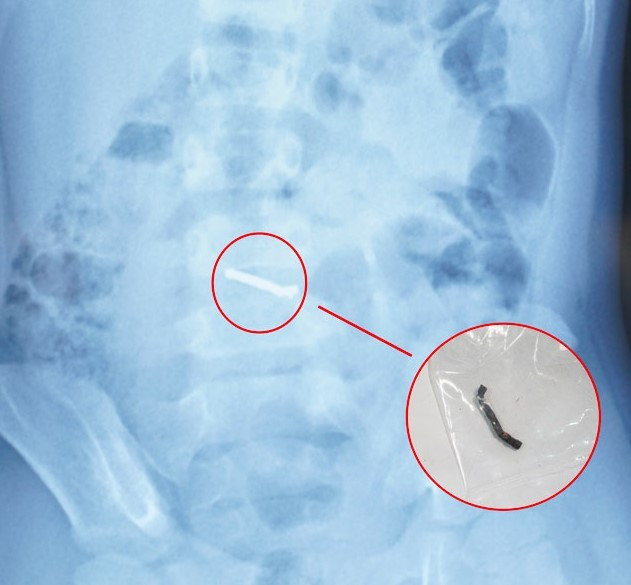

vien-bi.jpg

Hình ảnh dị vật qua chụp X-quang và viên nam châm sau khi được các bác sĩ phẫu thuật lấy ra.